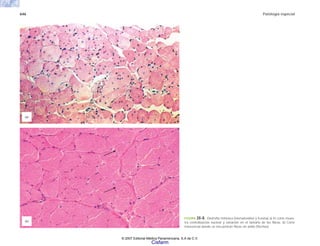

riñón

renina